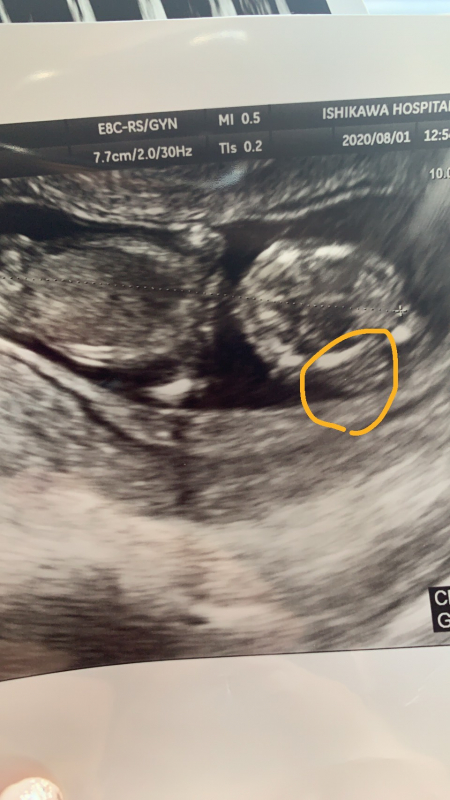

現在私が31歳。妊娠13週ですが、先週の土曜日の検診の際に、『赤ちゃんの頭の一部に浮腫がある。リンパ管の浮腫みや、染色体異常の可能性も考えられる。来週また検診へ来てください、旦那さんは連絡付きますか?電話させてもらうかもしれない。』と言われました。また、身体全体の大きさも2週間ほど小さいようです。 不安になり、ネットで調べてみると、首の後部浮腫はよく出てくるのですが、頭の浮腫はなかなか出てこず困惑しています。赤ちゃんにどのような事がおこっているのでしょうか。。ちなみに浮腫は1.5ミリか1.5センチかどちらかです…動揺していて単位が分からなくなってしまいました。ダウン症や18トリソミーの疑いもなくはないでしょうか。写真から何か分かることはありますか?

エコーで、赤ちゃんの頭の浮腫を指摘され、ご心配になりましたね。

お写真の掲載もありがとうございます。

実際にエコーを拝見していませんので、ハッキリとは明言できませんが、まだ妊娠初期ということもありますし、詳細な検査や経過を見ていかなければ分からないこともあるかと思います。医師から、リンパ管の浮腫や染色体異常の可能性があると指摘されたということであれば、そららの検査をしてみての判断になるかと思います。ご心配なところご相談いただきましたのに、まだ詳しいことが分からないので、なかなかはっきりとお答えすることができず、とても心苦しいですが、まずは経過を見て、医師にもよく説明を受けられてみてくださいね。